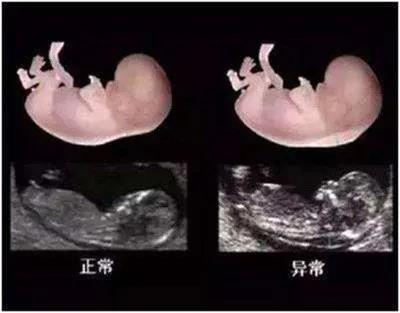

NT是胎儿颈部半透明膜的缩写,是10~13孕周围绕在胎儿颈项后部流动性的半透明蛋白膜。它的厚度与胎儿DS缺陷正相关,并可以通过超声成像测量。NT检查便于及早发现唐氏儿、先天性心脏病和其他结构畸形的胎儿,并及时予以干预。

报告中NT的数值含义

NT增厚越明显,胎儿异常机会就越高,异常程度也会越严重。般正常的NT厚度不能大于3mm,当大于3mm时约10%会发育为异常胎儿;当大于6mm时,这个异常程度会大大增加,约90%会发育成异常胎儿。